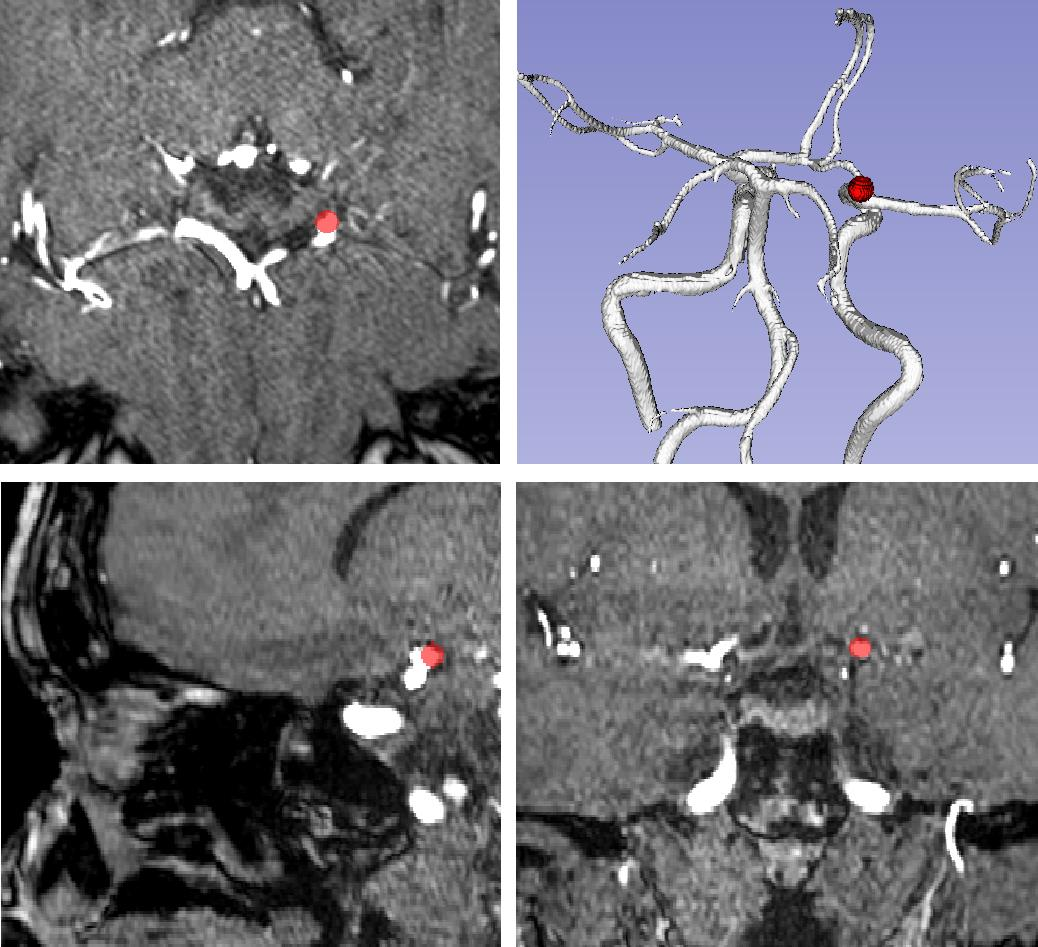

Supervised segmentation algorithms yield state-of-the-art results for automated anomaly detection. However, these models require voxel-wise labels which are time-consuming to draw for medical experts. An interesting alternative to voxel-wise annotations is the use of weak labels: these can be coarse or oversized annotations that are less precise, but considerably faster to create. In this work, we address the task of brain aneurysm detection by developing a fully automated, deep neural network that is trained utilizing oversized weak labels. Furthermore, since aneurysms mainly occur in specific anatomical locations, we build our model leveraging the underlying anatomy of the brain vasculature both during training and inference. We apply our model to 250 subjects (120 patients, 130 controls) who underwent Time-Of-Flight Magnetic Resonance Angiography (TOF-MRA) and presented a total of 154 aneurysms. To assess the robustness of the algorithm, we participated in a MICCAI challenge for TOF-MRA data (93 patients, 20 controls, 125 aneurysms) which allowed us to obtain results also for subjects coming from a different institution. Our network achieves an average sensitivity of 77% on our in-house data, with a mean False Positive (FP) rate of 0.72 per patient. Instead, on the challenge data, we attain a sensitivity of 59% with a mean FP rate of 1.18, ranking in 7th/14 position for detection and in 4th/11 for segmentation on the open leaderboard. When computing detection performances with respect to aneurysms' risk of rupture, we found no statistical difference between two risk groups (p = 0.12), although the sensitivity for dangerous aneurysms was higher (78%). Our approach suggests that clinically useful sensitivity can be achieved using weak labels and exploiting prior anatomical knowledge; this expands the feasibility of deep learning studies to hospitals that have limited time and data.